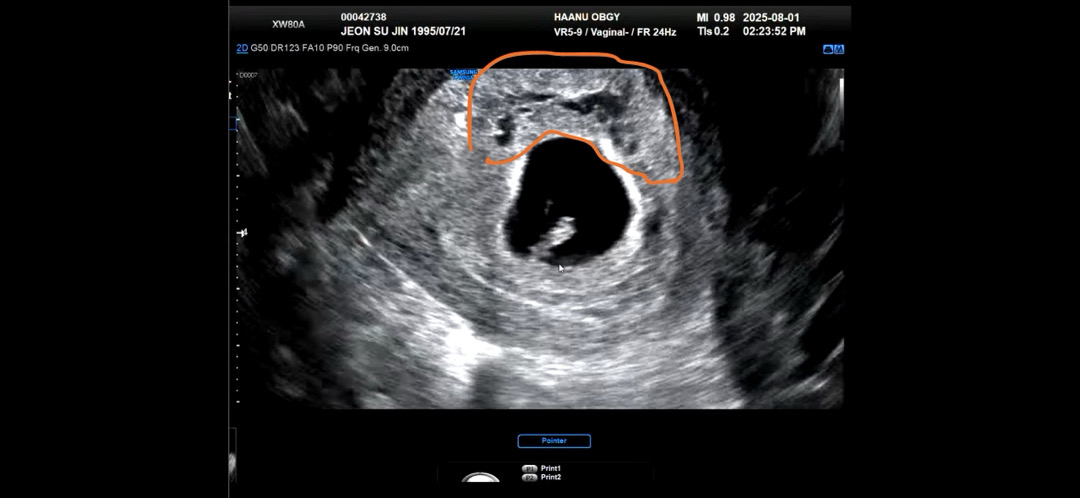

혹시 이게 피고임인가요..?

병원에선 별말 없었는데 저런건 뭔가요..?

피고임은 더 부피감?이 있고 작은 아기집처럼 보이더라구요~ 의사선생님이 별 말씀 없으셨다면 신경안쓰셔도 될 것 같아요~

피고임이아니라 난포아닌가여?